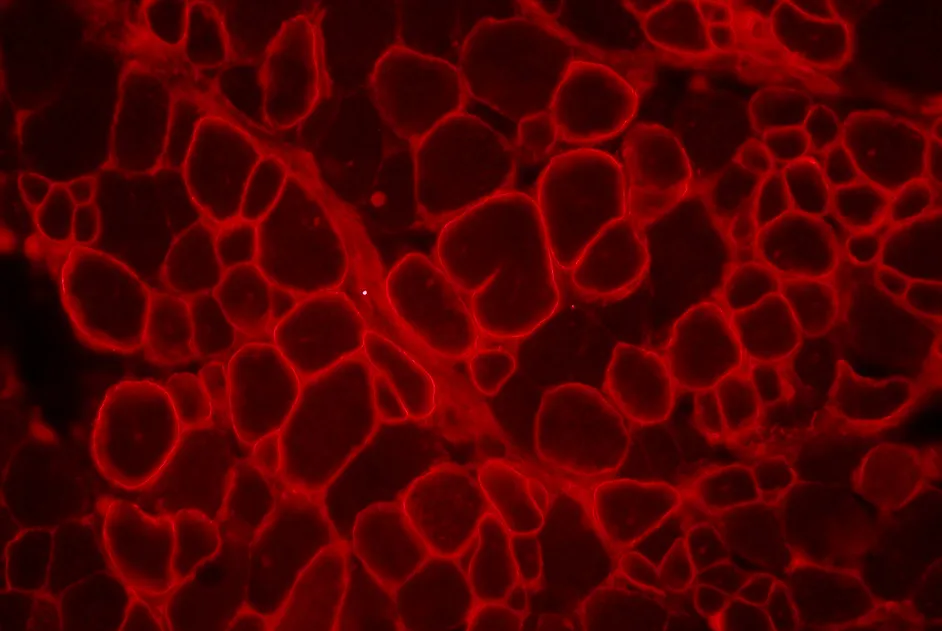

Recherche : développement d'une thérapie génique pour la calpaïnopathie

Une nouvelle étape a été franchie par des chercheurs à Généthon dans la mise au point d'une thérapie génique pour soigner la calpaïnopathie, une maladie rare des muscles.